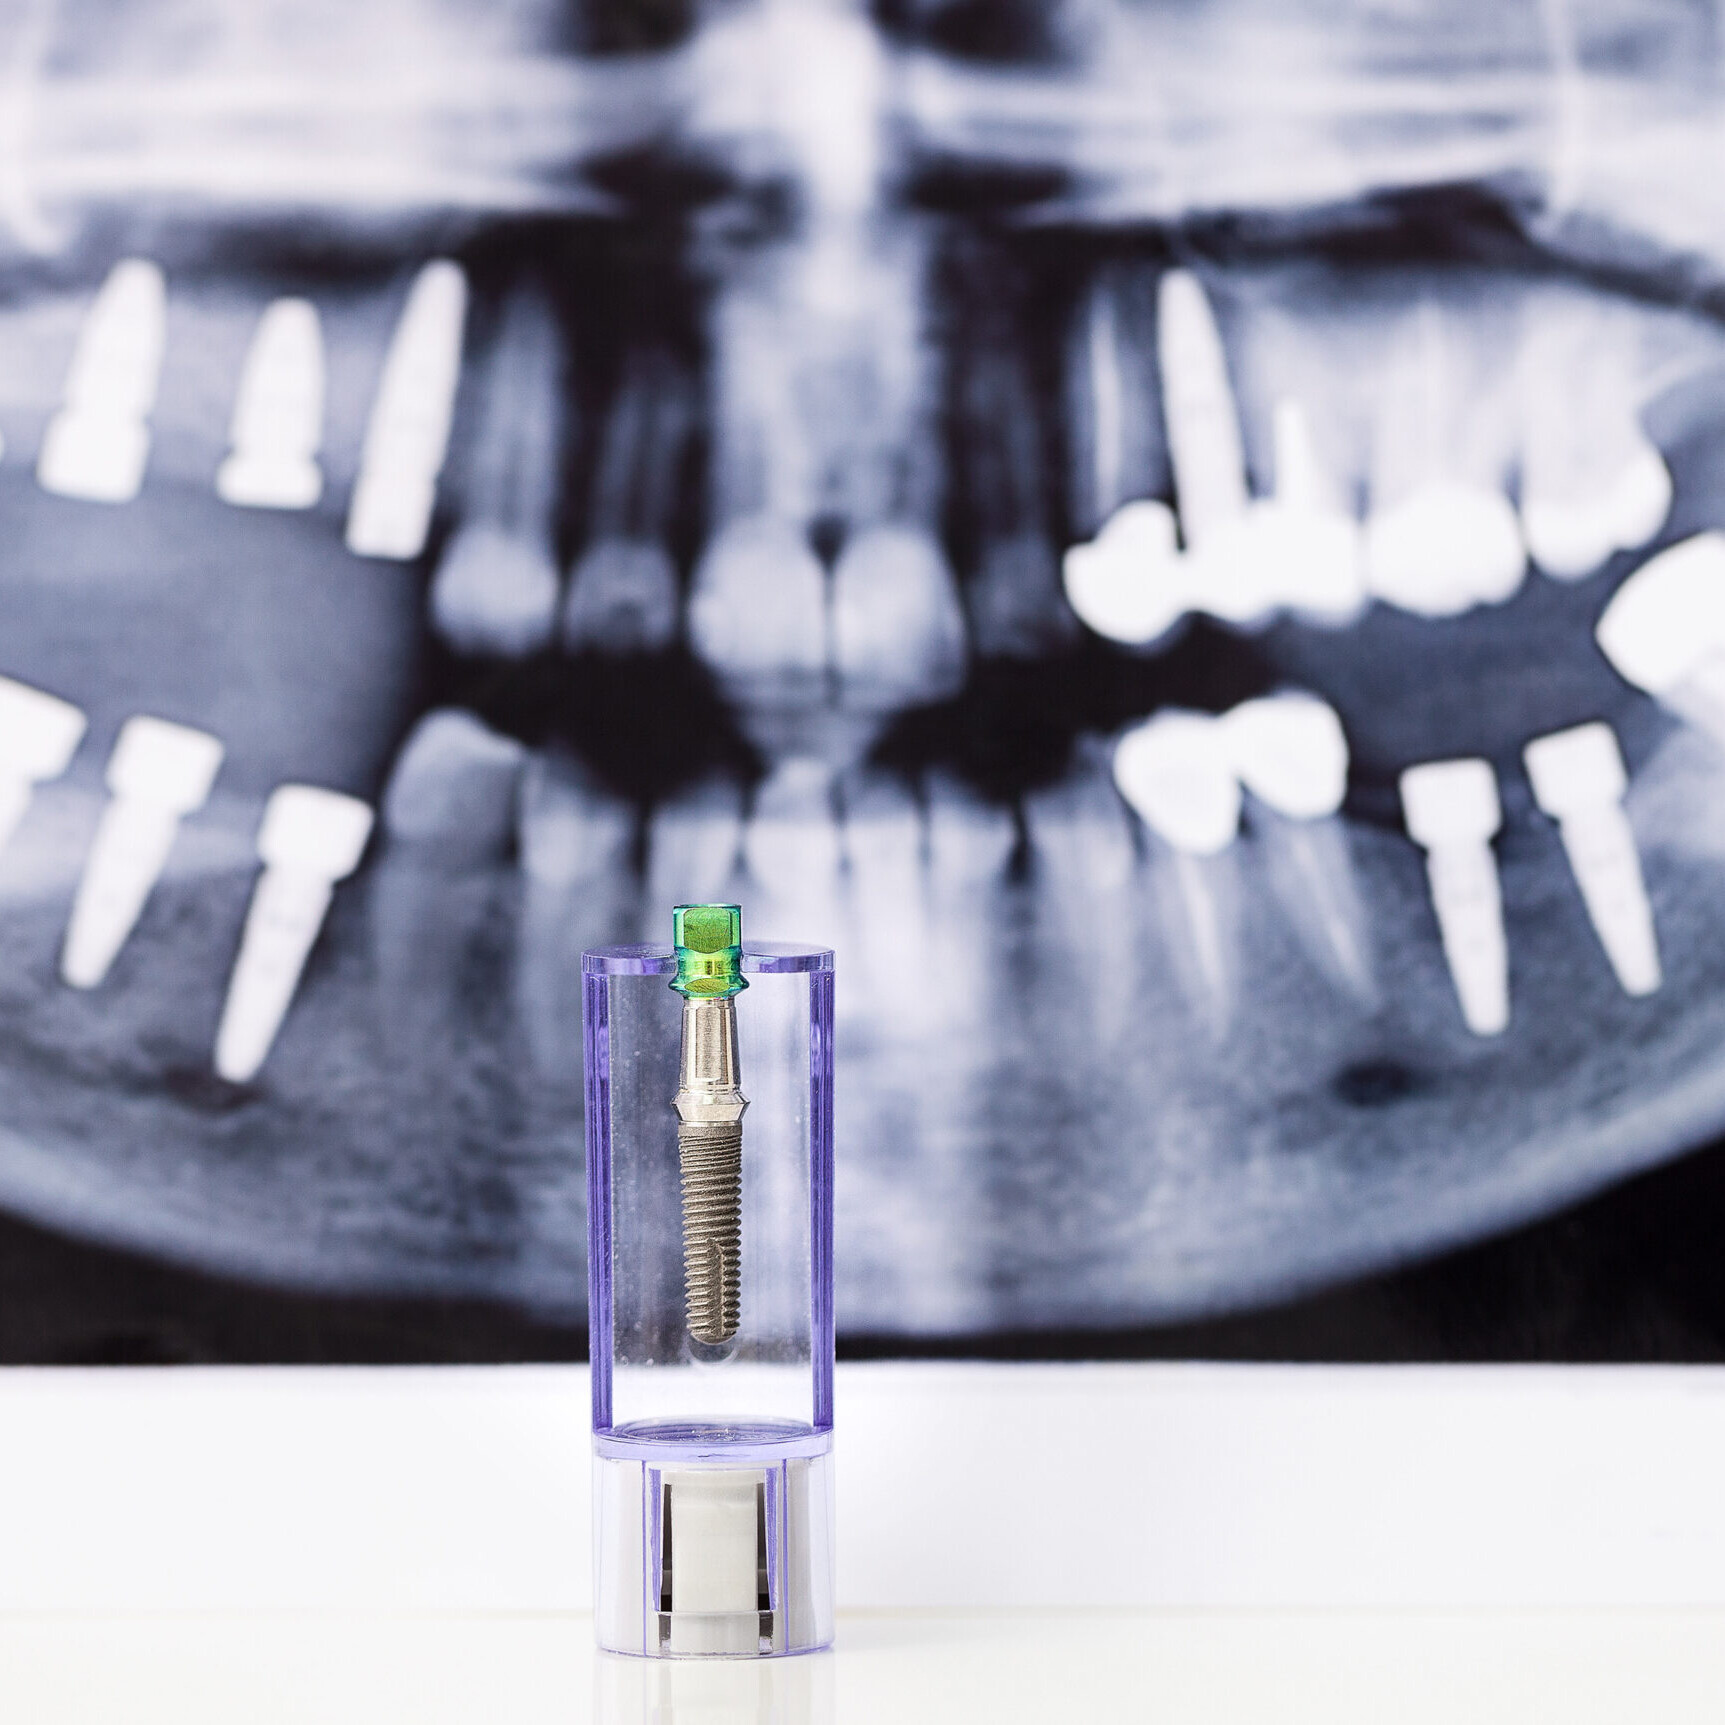

Nel nostro studio vengono proposte molteplici soluzioni di tipo protesico che spaziano dagli impianti osteo-integrati ad ogni tipo di protesi sia fissa che mobile.

Nel nostro studio vengono utilizzati impianti Straumann, oxy implant e kalodon.

Nel nostro studio vengono utilizzati solo impianti di altissima qualità per i quali viene fornito al paziente un passaporto implantare che consente di potersi rivolgere a qualsiasi studio dentistico in tutta Europa, in casi di emergenza.